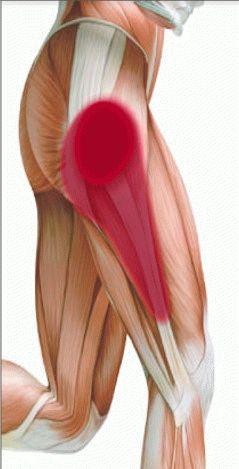

Здоровье суставов: Трохантерит и его влияние на мышцы